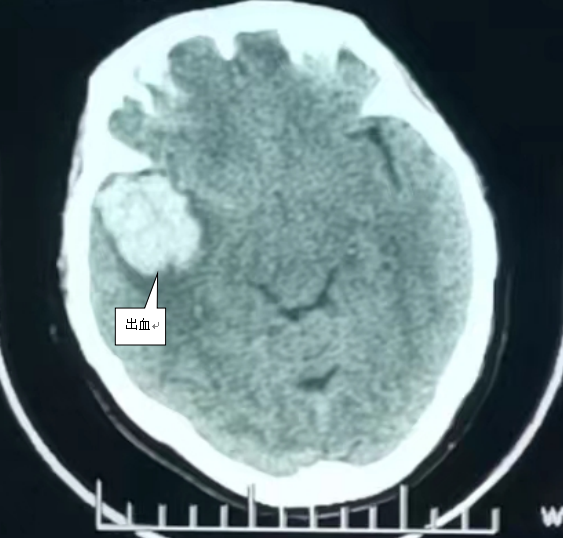

灰白色高亮影为颅内出血